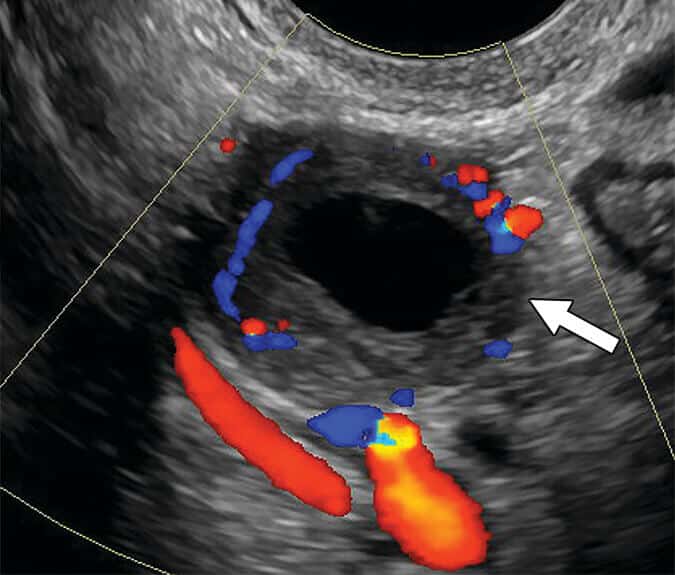

Ademais, como a vascularização é um elemento importante para definir o risco em algumas dessas lesões, utiliza-se a pontuação de cores (PC), um sistema numérico de 1 a 4 que quantifica o fluxo sanguíneo detectado ao Doppler, variando desde ausência de fluxo (PC 1) até vascularização intensa (PC 4).

Essa pontuação só influencia a classificação de risco em três situações específicas: lesões sólidas de contorno liso, lesões císticas multiloculares com componente sólido e lesões císticas multiloculares sem componente sólido, mas com paredes internas ou septos lisos.

Nos cistos multiloculares que apresentam componente sólido, a classificação entre O-RADS 4 e O-RADS 5 depende exclusivamente da avaliação do fluxo ao Doppler.

Quando o fluxo é ausente ou muito discreto, a lesão enquadra-se como O-RADS 4. Já quando o Doppler mostra vascularização moderada ou intensa, o risco de malignidade aumenta, e o cisto classifica-se como O-RADS 5.